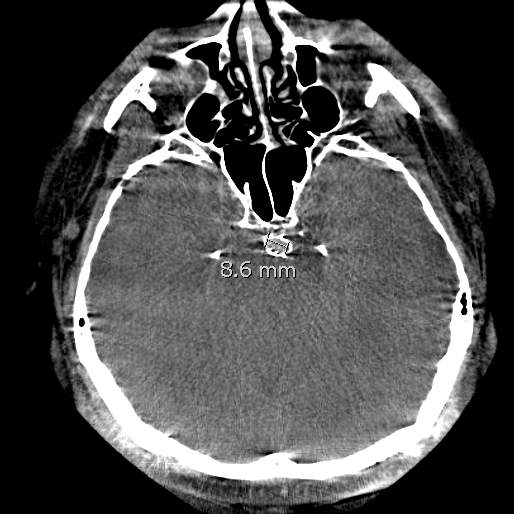

椎基底动脉冗长扩张症,是最棘手最复杂的脑血管病之一。患者从外地千里迢迢(3900余公里,仅高铁41小时)赶来东方医院诊治,期间症状不断加重(图2非真实大小)。术后一周复查:1、右侧肢体肌力明显改善;2、右侧肢体和枕部麻木症状明显改善;3、饮水呛咳缓解;4、共济失调明显改善;5、流涎消失;6、消失的味觉再次恢复。术后一周复查:血管修复良好(图5)。期待患者早日康复,早日奔赴工作岗位,保一方平安。